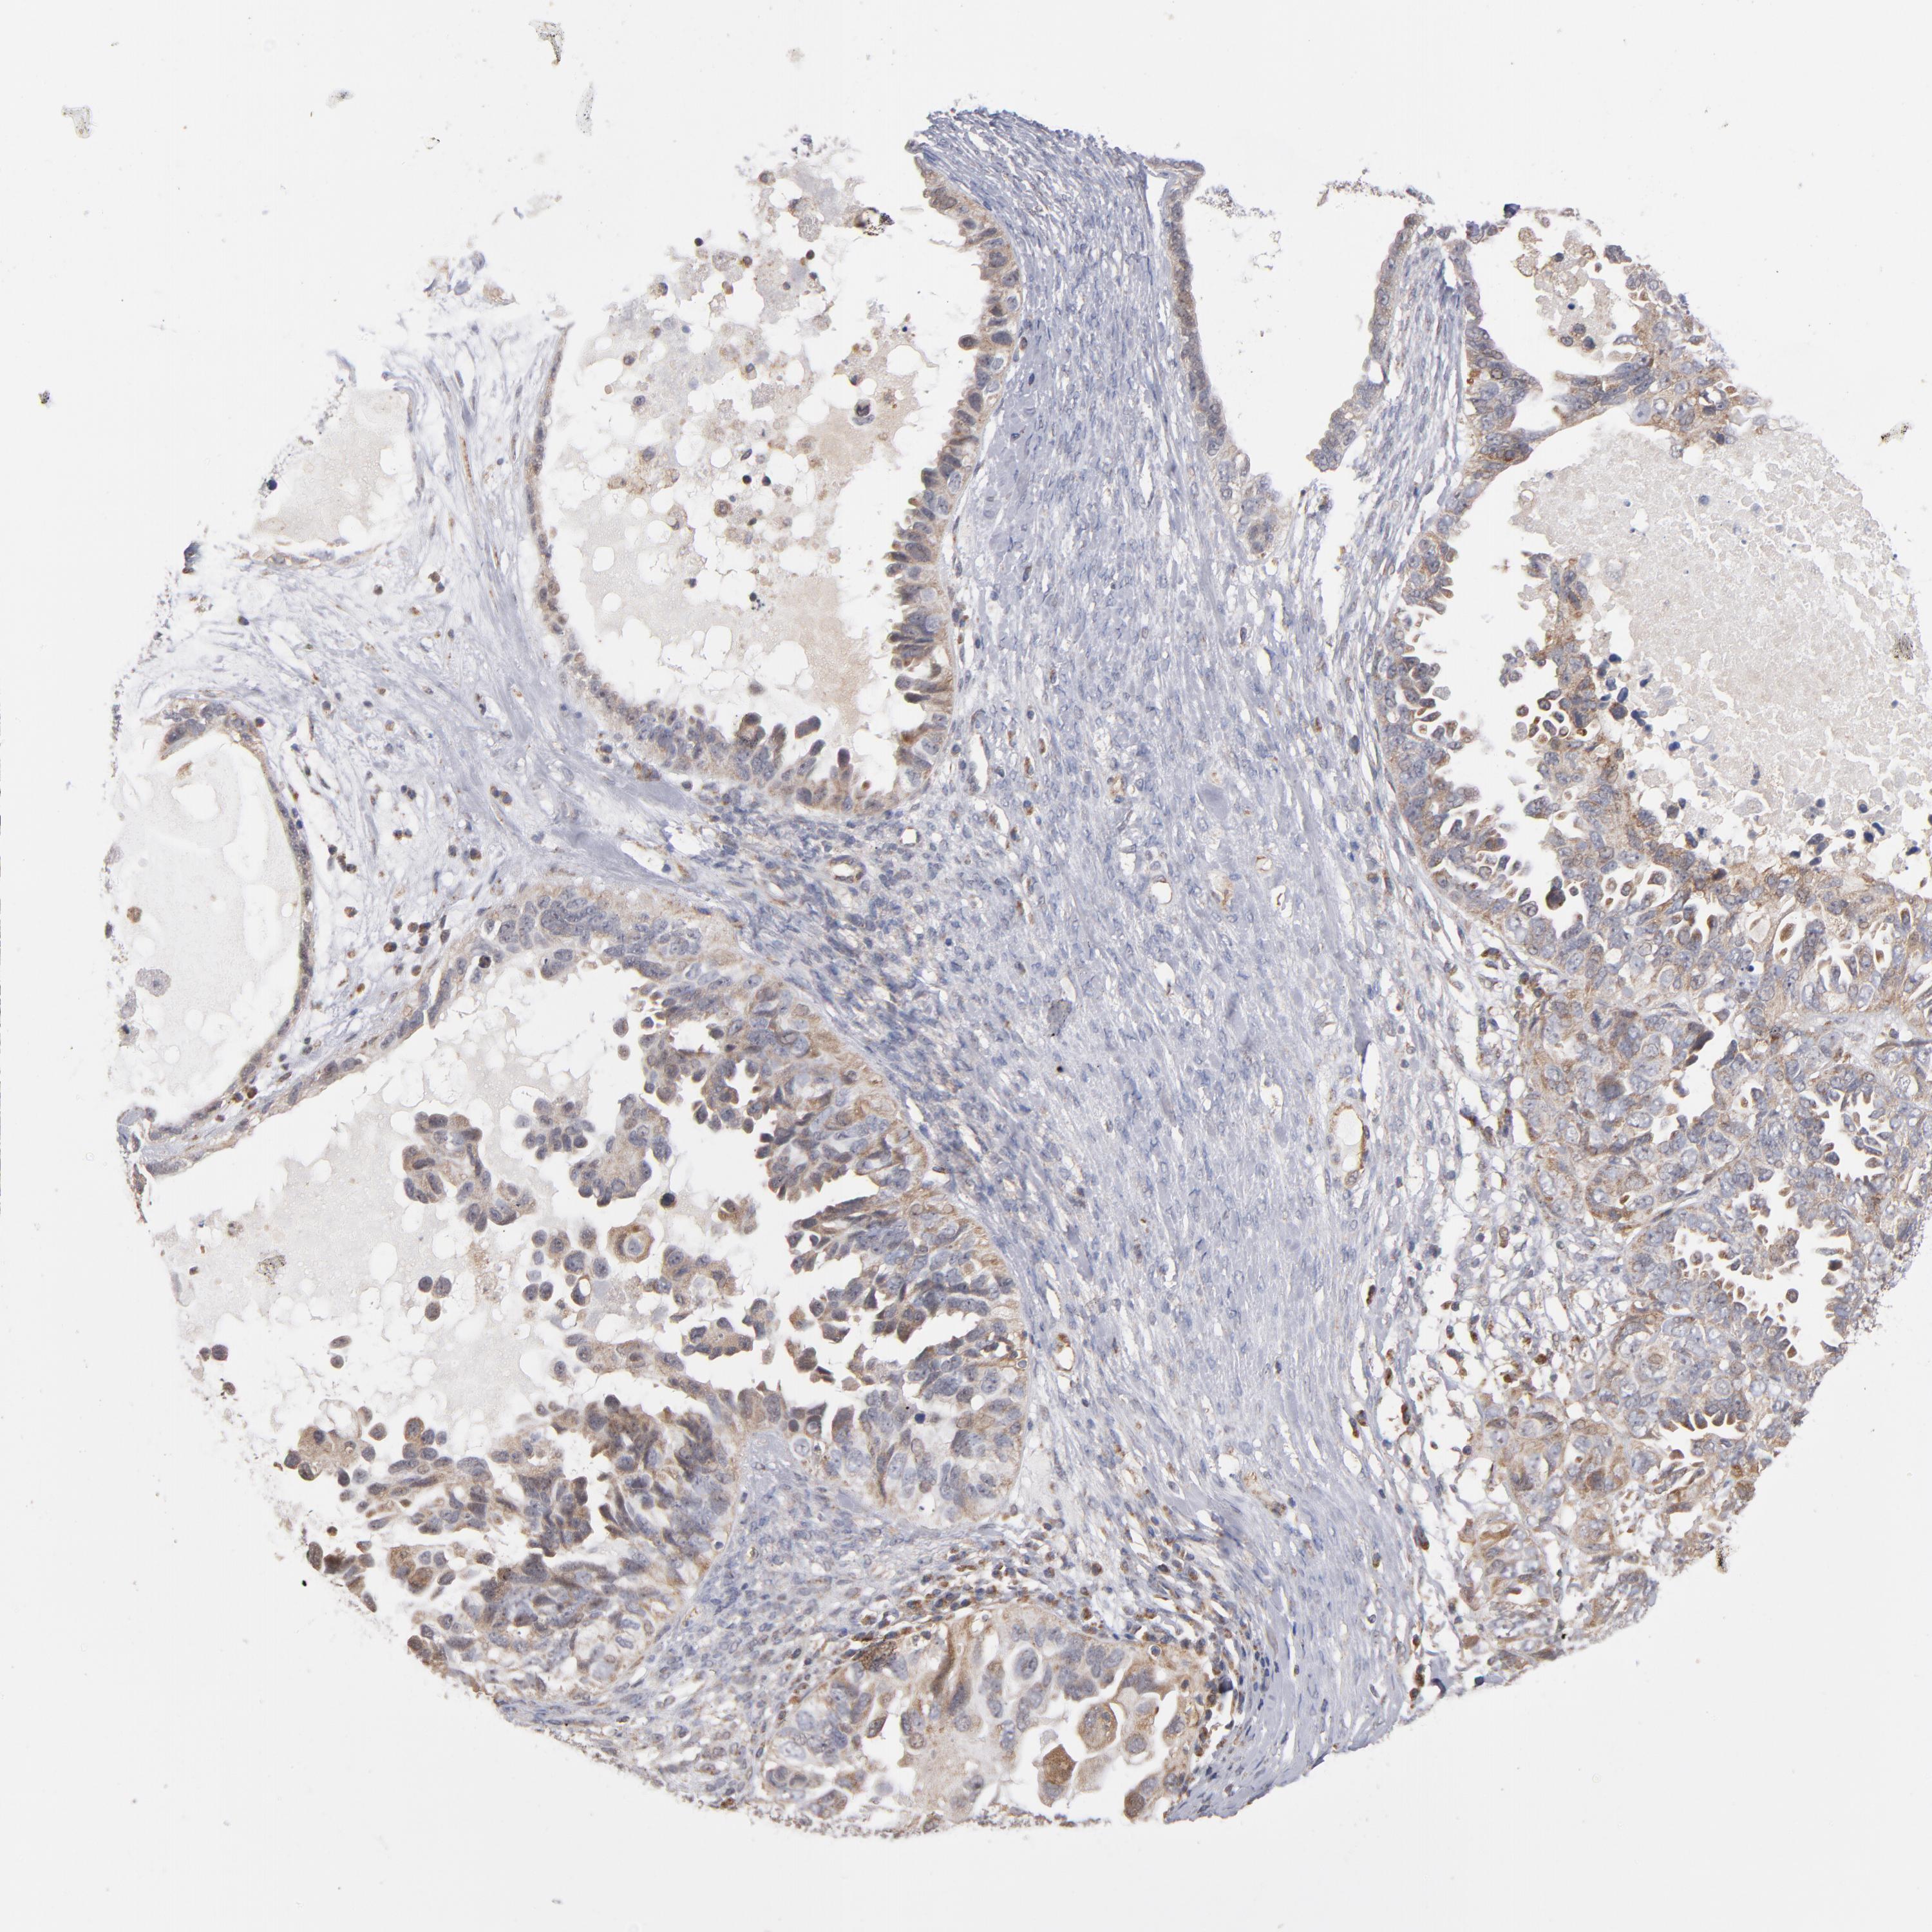

OVARIAN CANCER - Protein expressioni

A mouse-over function shows sample information and annotation data. Click on an image to view it in a full screen mode. Samples can be filtered based on level of antibody staining by selecting one or several of the following categories: high, medium, low and not detected. The assay and annotation is described here.

Note that samples used for immunohistochemistry by the Human Protein Atlas do not correspond to samples in the TCGA dataset.

Antibody stainingi

Antibody staining in the annotated cell types in the current human tissue is reported as not detected, low, medium, or high, based on conventional immunohistochemistry profiling in selected tissues. This score is based on the combination of the staining intensity and fraction of stained cells.

Each image is clickable and will lead to virtual microscopy that enables deeper exploration of all samples and also displays staining intensity scores, fraction scores and subcellular localization as well as patient and tissue information for each sample.

Antibody HPA002893

Staining

High

Medium

Low

Not detected

Intensity

Strong

Moderate

Weak

Negative

Quantity

>75%

75%-25%

<25%

None

Location

Nuclear

Cytoplasmic/membranous

Cytoplasmic/membranous,nuclear

Cystadenocarcinoma, serous, NOS

Cystadenocarcinoma, mucinous, NOS

Carcinoma, endometroid